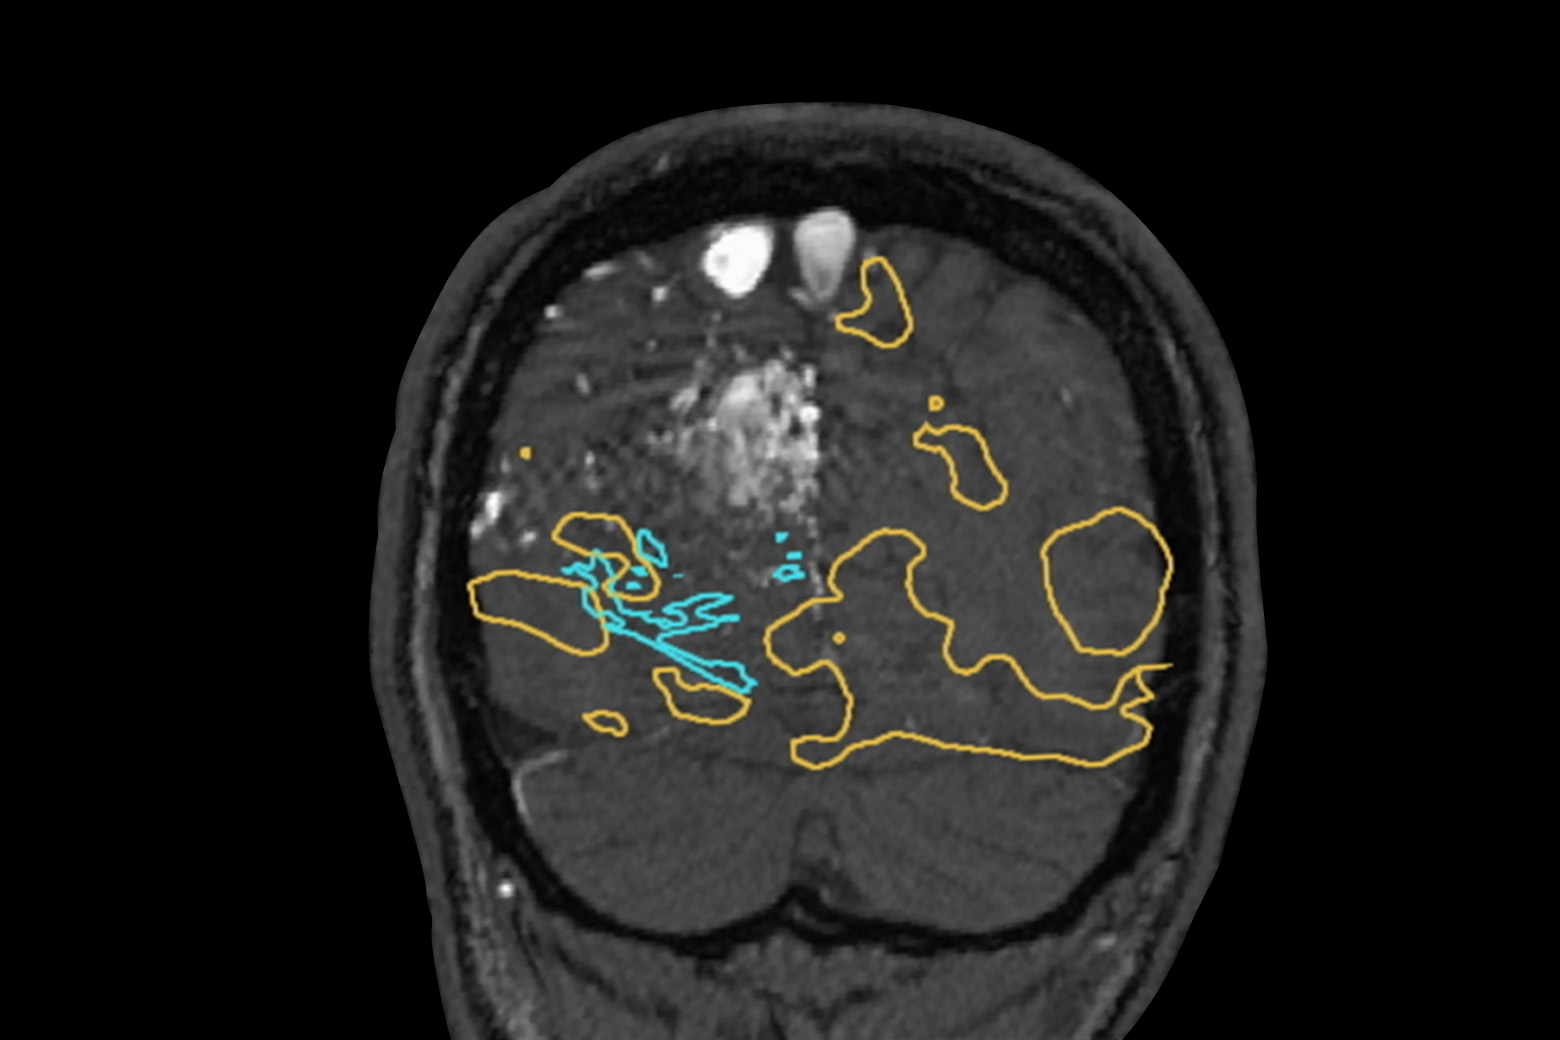

- Preoperative embolization reduced the size of the AVM nidus by about 50 percent.

In a preoperative embolization, Dr. Riina infused an ethylene vinyl alcohol copolymer dissolved in dimethyl sulfoxide into arterial branches feeding the patient’s AVM nidus. The procedure obliterated roughly 50 to 60 percent of the AVM nidus, as shown by an angiogram (Slide 3).